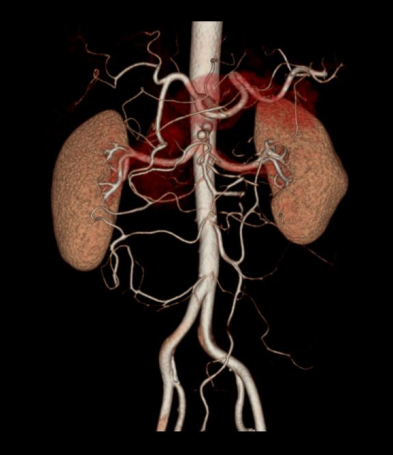

- 3d reconstruction of the renal arteries, abdominal aorta and common iliac arteries.

- Renal artery pre-hilar arterial branching distance measurements on curved MPR or on 3D images, separately for both renal arteries.

- Renal artery diameter measurements from abdominal aorta to first branching on proximal, mid and distal points.

- MIP images through the kidneys to show small accessory renal arteries.